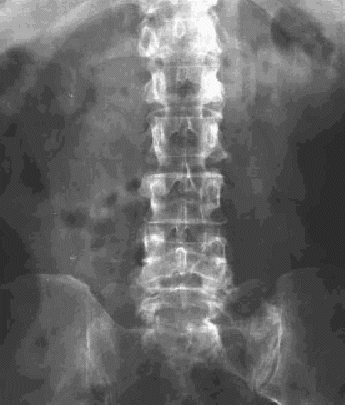

Figura 19.—Radiografía anteroposterior de columna lumbar: Fracturas de todas las apófisis transversas derechas y 3.ª-4-ª izquierdas. Anomalías congénitas: hipoplasia bilateral de las 12.ª costillas y sacralización de L5.